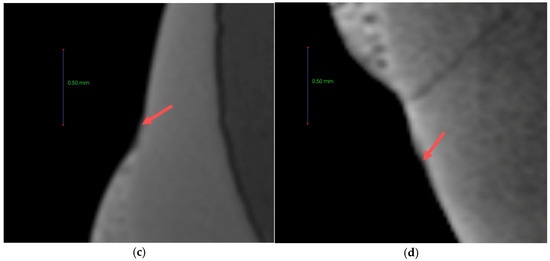

3.8. Anti-demineralization